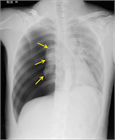

1. 一般的な気胸の重症度分類シェーマ図を追加した。

1. 患者のバイタルと胸部X線検査で肺虚脱度を確認し、バイタルの異常や虚脱の程度で治療方針を決定する。